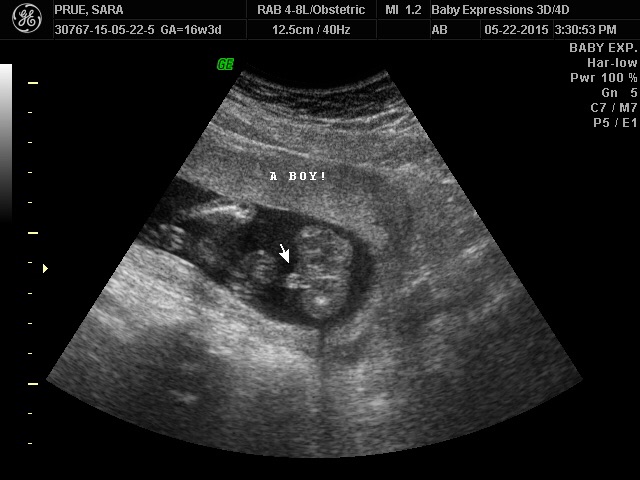

I got a 3D ultrasound at 16 weeks and they were able to tell me the sex! A boy with 100% confidence..:mainly because the penis was just hanging out there. I did it for fun and not in place of.

I went to an independent ultrasound place yesterday morning and I am 16 weeks. They included 4D images, a DVD and a live internet stream for my family who lives 1,300 miles away in the package I purchased and it was amazing. Unmistakably a boy when we look at it in 4D. We will be going home next month. My husbands in the military and its the only time he gets leave and we will be able to see our families before the baby arrives. My sister wants to throw me a baby shower so that was my main reasoning for going, since my 20 weeks scan isn't until after my husbands leave dates. I had a great experience and recommend doing your research and not picking the first one you find. Ours was worth the money we spent to me, as our technician was amazing. She found the baby on the screen and put my husbands hand on my tummy and had him poke gently near baby's feet and had him "play" with the baby. He was kicking him right back and I've never seen my husband so happy. We wouldn't of had anything like that experience at my doctors office (:

I went to peek a belly here in IL at 15 weeks. We were able to know that we are having a little boy! Even if u waited to 20 weeks there is always a chance the tech could be wrong so I chose to pay the lil bit of money to find out sooner.